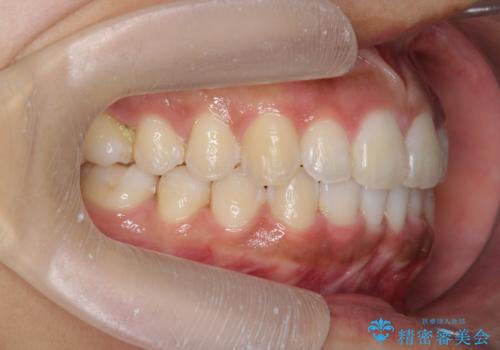

出っ歯感のある前歯を治したい、抜歯をしないマウスピース矯正

- 前歯のガタつき、突出感のある前歯の改善を求めて来院されました。

前歯の角度を改善し審美性を高めるとともに、奥歯のガタつきも並べ直すことで安定した咬合関係の確立を目指します。

歯列の側方拡大をしっかりと行ったことで歯を抜かずに前歯の角度をしっかりと改善することができました。